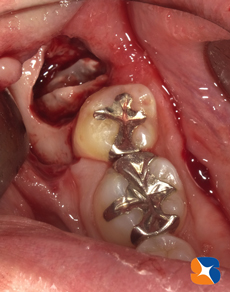

抜歯開始から1時間後、無事に取り出すことができました。根の先のほうが広がっていては、当然抜けませんよね。

特殊な器具と工具を使って、歯を2分割にして抜歯しました。